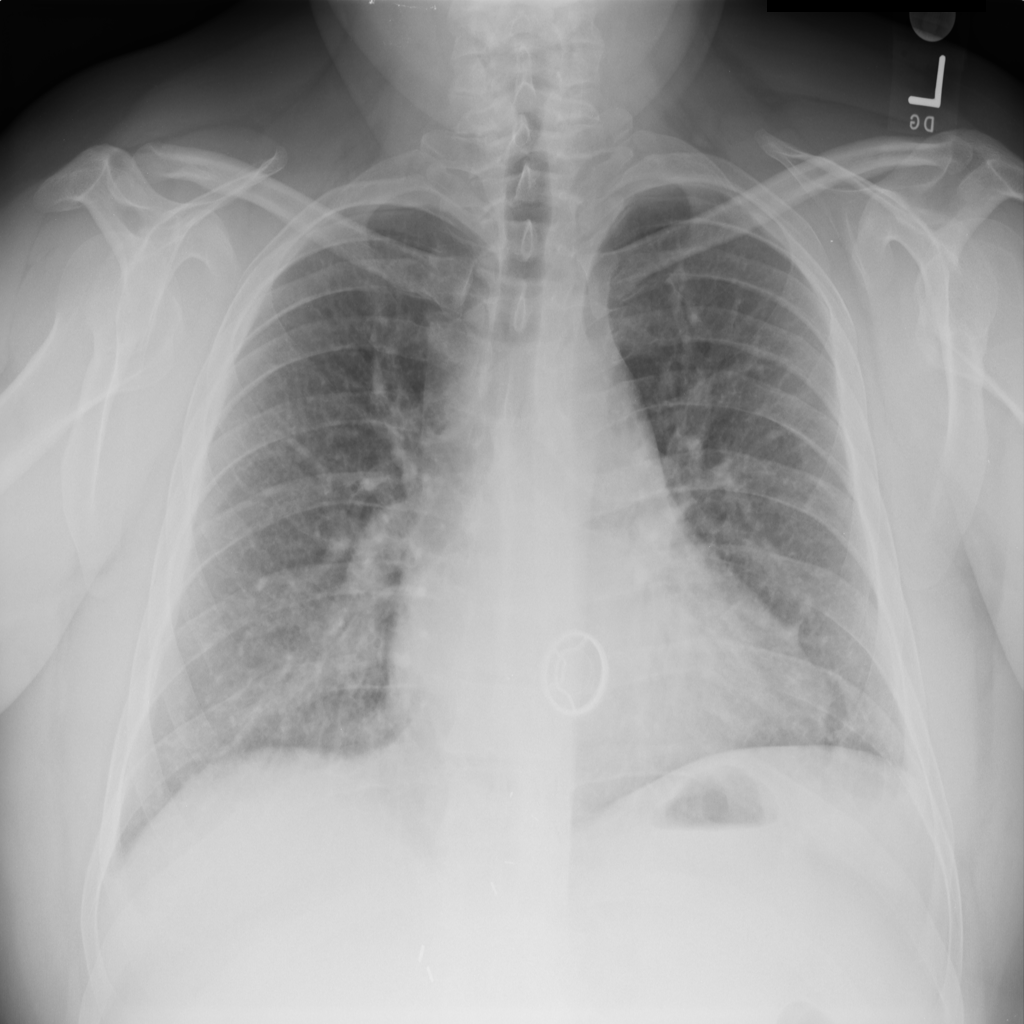

Cardiomegaly

Cardiomegaly means the heart appears enlarged on the chest X-ray. It is a descriptive imaging finding that can be related to heart strain, chronic pressure or volume changes, or even projection effects.

Showing up to 90 reference images for Cardiomegaly.

PAT-AE5C · IMG-000Cardiomegaly

PAT-AE5C · IMG-000

PA